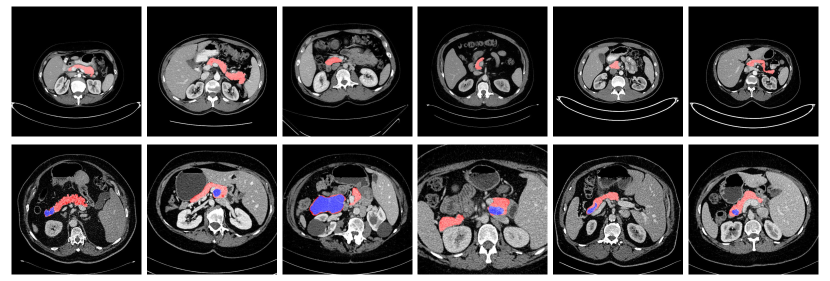

Refer to caption

Figure 1: An illustration of normal pancreases on NIH dataset roth2015deeporgan and abnormal cystic pancreases on JHMI dataset zhou2017deep shown in the first and second row respectively. Normal pancreas regions are masked as red and abnormal pancreas regions are marked as blue. The pancreas usually occupies a small region in a whole CT scan. Best viewed in color.